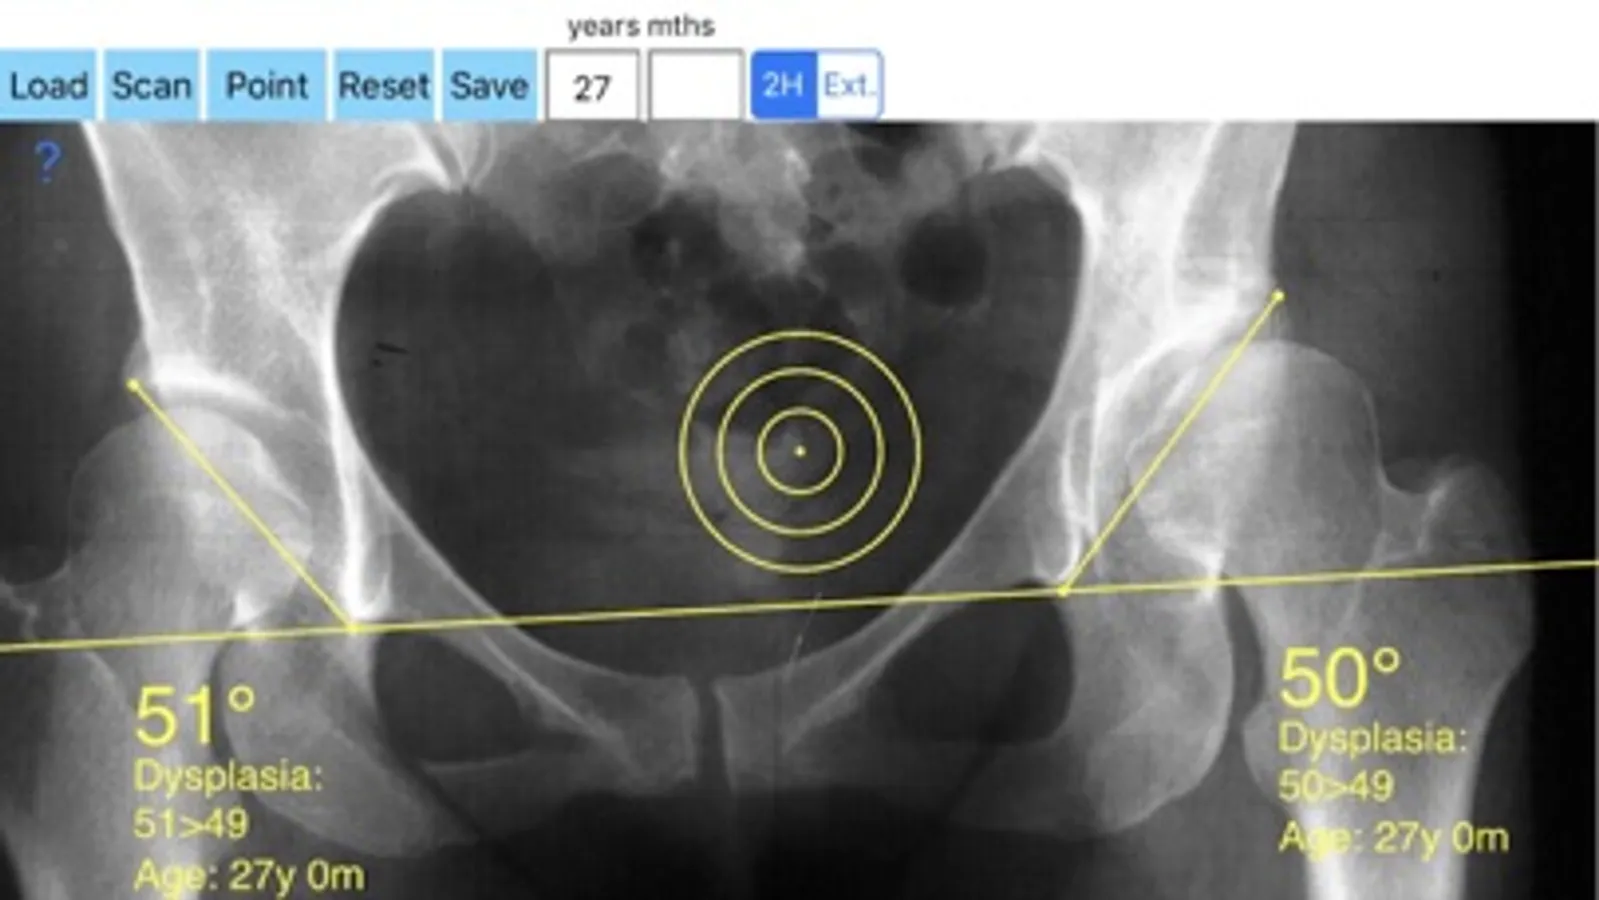

-Securely import medical images directly from the camera or stored photos

-Offers a very convenient way to determine the most accurate possibly lines in order to measure the angles. By the aid of a circular transparent template, the points of interest are marked accurately. The automatically formed lines, drawn between points, measure automatically the angles of interest. The results are printed in degrees. By inputing the age, of the patient in the App, the measured angle is compared with values from normal reference database according to patient age. In case the measured angle is beyond the normal range for that age, the hips are categorised as borderline dysplastic or dysplastic.

The app is a handy tool for an orthopaedic surgeon, radiologist, medical student or resident who wants objectively monitor and determine the severity of dysplasia of the hip. The build-in comparison feature with the normal reference values according to patient age may help decide what could be considered normal or borderline dysplastic or dysplastic. The app is not a simple goniometer, is an enhanced product which offers the ability to compare all the input data with medical reference database. The results are printed on the screen and the hips are categorised as normal or dysplastic according to the AA angle measures respectively. This feature it is particular useful especially in clinical settings where you need a quick results without losing time in looking for reference data according to age variations in huge textbooks.